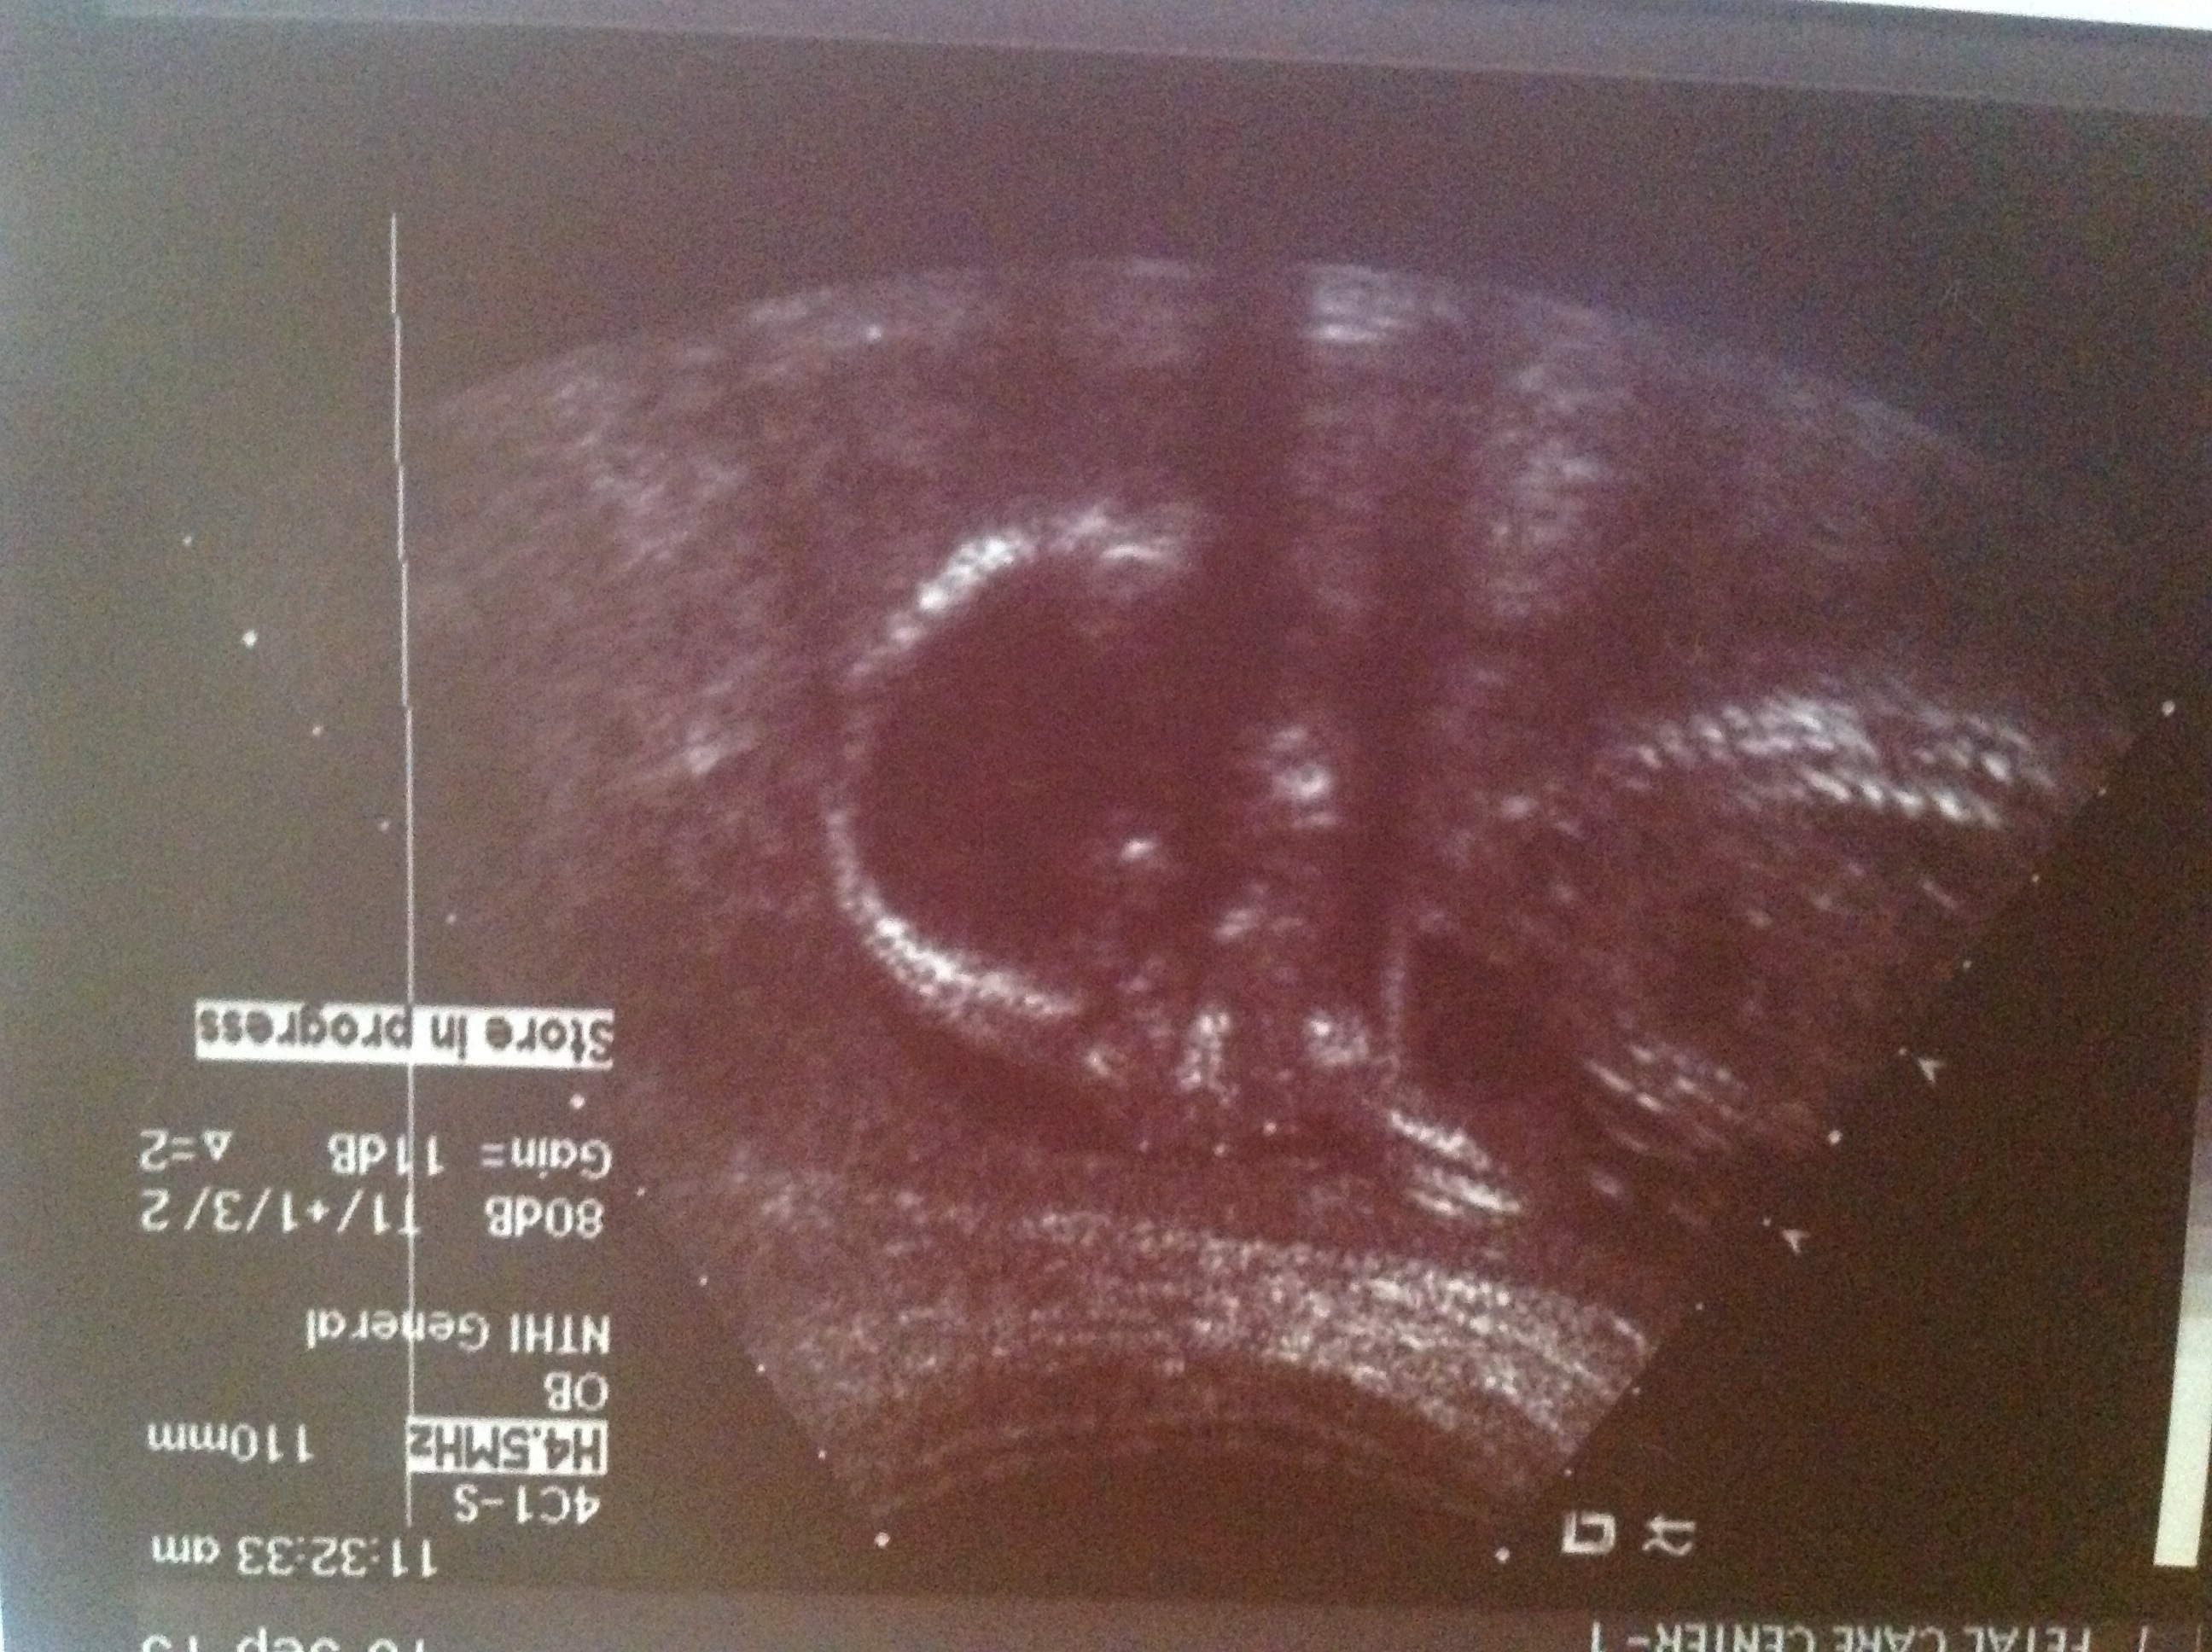

I have a beautiful profile of my little baby at 19w3d. We haven't found out the gender yet, but we have it in an envelope... We were thinking of staying team green, but now I think we'll look at our envelope in a month or two (or maybe sooner).

Any skull theory guesses just for fun? I don't think skull theory is particularly accurate, but I can't help being curious about what people would guess!